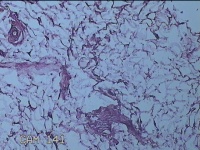

后枕部包块

性别

男

年龄

40岁

临床诊断

头部脂肪瘤

一般病史

发现后枕部包块2年俞,无疼痛基本。

标本名称

大体所见

灰白暗红色包块2.5x2x1.3cm一个,表面光滑,切开包块呈实性,切面灰白淡黄色,质软。